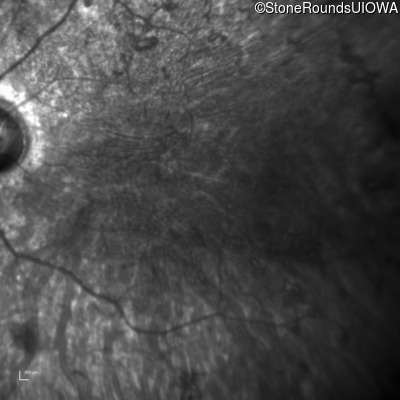

Infrared Fundus Photograph - Right - <1/700 sc

Exemplar